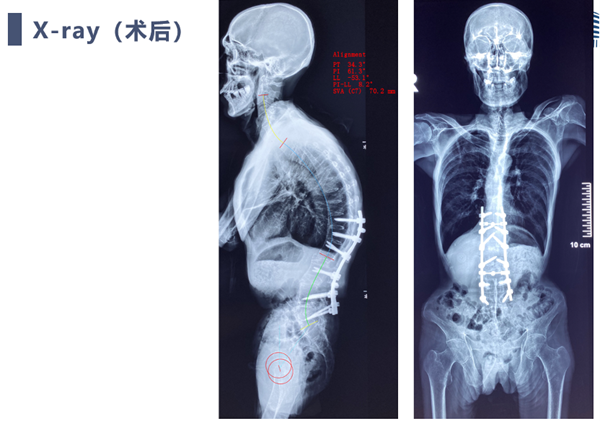

术后复查

强直性脊柱炎后凸矫形手术患者脊柱自我代偿能力基本丢失,术前需要精确的评估及手术计划来确保患者术后平视,坐立,平卧等基本需求。

本例患者重度营养不良,体重只有35公斤,需要严格控制出血量,本例患者采用显微镜辅助双节段COWO截骨,出血少,矫形效果良好。

对于强柱患者矫形过程需要防止ST(矢状位移)发生,避免脊髓损伤,本例患者采用保留部分骨连接,交叉上棒与体位复位相结合方式,复位过程安全平稳,无脊髓损伤发生。